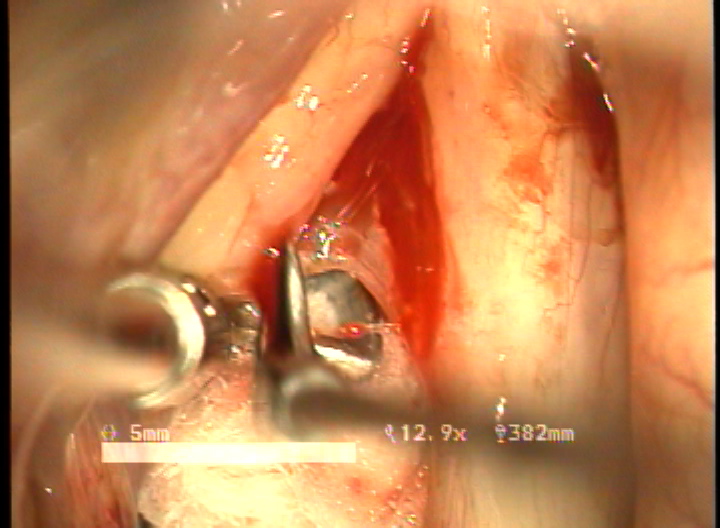

목적 : 전성문횡격막(anterior glottic web)은 선천성이나 수술과 같은 이차적인 원인에 의해서 발생되는 난치성 후두질환이다. 또한 기존의 치료방법으로는 음성개선의 효과가 매우 낮은 결과를 얻고 있다. 이에 음성의 보존과 함께 일차적 시술로서 치료가 가능한 double rotation microflap 을 이용한 새로운 술식을 보고하며, 이술식의 치료결과와 음성학적 개선을 알아보고자 하였다.

방법 : 2006년 1월 부터 2007년 12월 까지 예송이비인후과에서 전성문횡격막으로 진단되어 double rotational microflap laryngoplasty를 시행받고 1년간 장기추적이 가능하였던 6명의 환자를 대상으로 후향적 분석을 시행하였다. 원인적인 요인과 동반질환으로는 후두유두종 술후 합병증 4례, 후두외상 1례, 폴립양성대 1례 였다. 남녀 각각 3례였으며, 평균연령은 39세 였다. 추적기간은 21.5 개월이었다. 술 후 2개월과 6개월에 음성개선에 대한 주관적인 음성평가를 시행하였으며, 음성분석검사와 후두스트로보스코피 검사를 통하여 객관적인 음성평가와 성대점막파동의 변화를 관찰하였다. 통계적 유의성은 Wilcoxon Signed Ranks Test로 검정하였다.

결과 : 음성개선에 대한 주관적인 평가로서 수술전 Voice Handicap Index는 평균 19.7 에서 술후 11.5로 감소하였다. 공기역학적인검사상 성문하압은 5.5에서 4.5로 감소되었으며, 최대발성시간 13.7에서 16.1로 증가되었다. 음성분석검사상 sPPQ, sAPQ, NHR, SPI, DSH가 모두 통계학적으로 유의하게 감소하였다. 후두스토로보스코피검사상 모든 례에서 재발의 징후없이 성대점막파동의 의미있는 호전이 나타났다. 합병증으로 1례에서 염증성 육아종형성이 관찰되었으나 미세피판의 괴사나 탈락은 관찰되지 않았다.

결론 : 전성문횡격막의 새로운 수술방법으로서 double rotational microflap laryngoplasty는 일차수술로 만족스러운 음성학적 치료결과를 얻을 수 있는 매우 유용한 술식이라 사료된다.